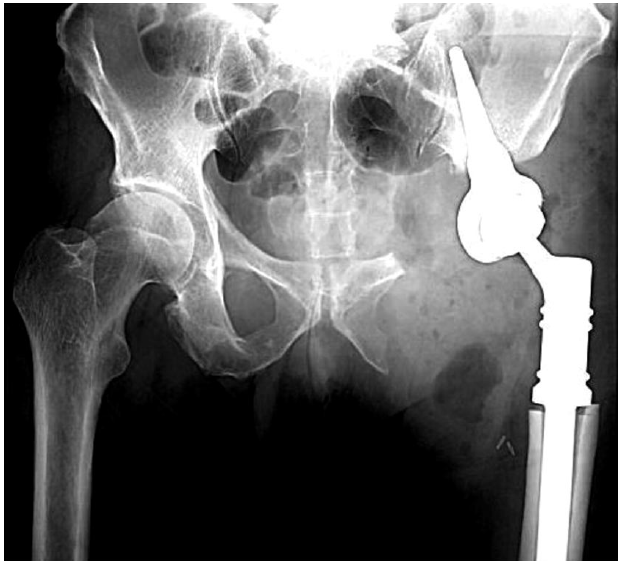

Рис. 1. КТ костей таза и магнитно-резонансная томография костей таза пациента с метастатическим поражением параацетабулярной области до проведения хирургического лечения.

Fig. 1. CT of pelvic bones and a pelvis magnetic resonance imaging scan of the patient with para-acetabular part metastases before the surgical treatment.

Рис. 2. Рентгенография костей таза в прямой проекции после выполнения параацетабулярной резекции с эндопротезированием модульным эндопротезом на основе конической ножки.

Fig. 2. X-ray of pelvic bones in direct projection after para-acetabular resection with endoprosthesis replacement using modular endoprosthesis based on conical leg.